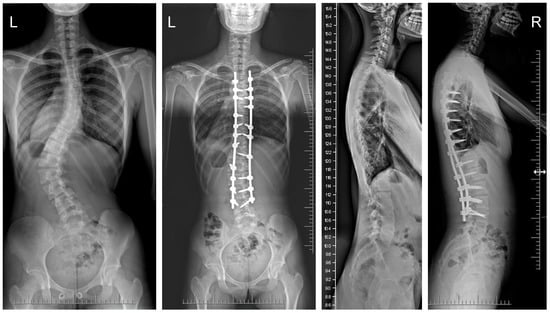

The mean (SD) operative times were recorded as 252 (62.4) minutes for the G1 patients and 344 (82.8) min for the patients in G2. The mean (SD) estimated blood loss levels were noted as 480 (288) mL for the patients in G1 and 632 (278) mL for G2. During statistical analysis, we found no statistically significant differences in either operative time or estimated blood loss between the study groups. The mean (SD) fusion levels were 10.2 (2.8) for G1, and 9.8 (3.2) for G2 (N.S.). The mean (SD) screw densities were noted as 75% (12) for the G1 group, and 75 (10) for the G2 group (N.S.). All analyzed data are presented in Table 1. Figure 1, Figure 2, Figure 3 and Figure 4 show X-rays of exemplary patients with idiopathic scoliosis after surgical treatment from G1 and G2.

Figure 2.

X-rays of a 16-year-old girl with AIS, treated with selective thoracic fusion. A smaller (standard) screw size of 5.5 mm and 2 titanium rods of 5.5 mm (G1) were used. X-rays show curve before surgery and correction after surgical treatment.

The correction of spinal deformities using modern systems based on the CD technique enriched with osteotomy techniques of the posterior column of the spine provides powerful opportunities for the correction and stabilization of curvatures [4,8,10,11,12,13]. Many details of implants have evolved and been improved, such as the implant profile, screw head stiffness, mobility in the sagittal axis, and its multi-axial nature, to obtain the best possible correction results [20,21,37,38]. The quality of the rod used is important in three-plane correction, i.e., the metal alloy (titanium, cobalt–chrome) and its diameter, which affects its ability to reproduce the sagittal and frontal balance of the spine [17,18,19,20,21]. It is known from other biomechanical studies that the larger the screw diameter, the better the stabilization and the lower the risk of screw removal and implant loosening [20,23,39,40,41]. For the surgical treatment of AIS, we received excellent outcomes using a system based on CD instrumentation in terms of three-dimensional correction of the spine (Figure 1, Figure 2, Figure 3 and Figure 4 show X-rays of exemplary patients with idiopathic scoliosis after surgical treatment from G1 and G2), the coronal and sagittal planes, derotation, and the clinical outcomes [11,12,13]. It should be emphasized that the correction possibilities of spinal deformation are influenced by other factors that we did not analyze, such as bone quality, so we focused on assessing the results of surgical treatment based on the sizes of the screws and rods used [39,40,41]. Also, the flexibility of the spine assessed on bending films is the main factor influencing the achievement of correction, as well as the loss of correction [42].